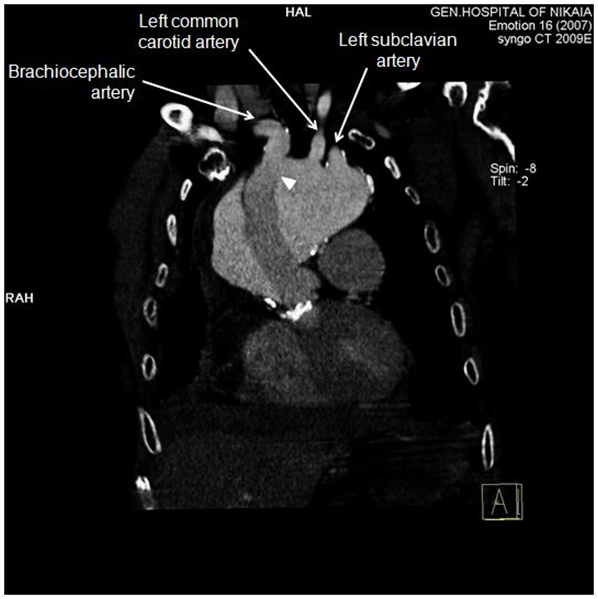

Clinical examination on admission revealed low blood pressure (80/50 mmHg), tachycardia (130 beats per minute) and hypoxia (oxygen saturation 90% with nasal cannula). Auscultation of the lung fields exhibited wet rales and absence of respiratory sounds, mainly at the base of the right lung. Heart sounds were muffled, however the closing click of the prosthetic aortic valve was distinct. The electrocardiogram (ECG) showed multiple disturbances, i.e. sinus tachycardia, right bundle branch block (RBBB) pattern, left anterior hemiblock (LAH) pattern, and T-wave inversion at infero-lateral leads. Jugular venous distention was also noticeable. A chest X-ray revealed an extensive mediastinum widening, aortic knuckle dilatation and right pleural effusion (Figure 1). A rapid transthoracic echocardiography (TTE) carried out in the emergency room confirmed that the proximal edge of the prosthesis was firmly attached to the left ventricular outflow tract, and the aortic valve was properly working. Blood tests demonstrated anemia (Hb 8.2 gr/dl), mild renal impairment (creatinine clearance 84 ml/min) and a slight rise of troponin I levels (0.55 ng/ml).

Figure 1 Patient’s chest X-ray on admission. Extensive mediastinum widening, aortic knuckle dilatation and right pleural effusion are evident.